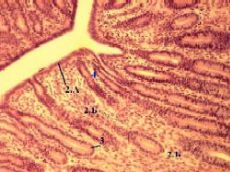

| 5,а-в. Препарат - матка кошки; поперечный разрез. Окраска гематоксилин-эозином. |

| На поперечном разрезе просвет (1) матки кошки - очень узкий и имеет звёздчатую форму. |

| Тканевой состав | Эндометрий (2) выстлан однослойным призматическим эпителием (2А), под которым находится собственная пластинка (2Б) слизистой оболочки, - образованная рыхлой волокнистой соединительной тканью - и пронизанная многочисленными маточными железами (3). |

| Маточные железы | Маточные железы (3) образованы такими же железистыми клетками, какие содержатся в покровном эпителии, по морфологии являются простыми, трубчатыми (п. 7.4.2.2) и бóльшую часть времени неразветвлёнными (в предменструальном периоде возможно ветвление), ориентированы перпендикулярно к поверхности эндометрия, | |

распространяются на всю толщину эндометрия (даже подчас внедряясь в миометрий) и продуцируют слизь во второй половине менструального цикла (в период секреции). |